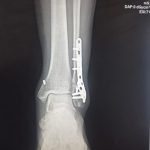

Orthopaedic Surgeon | Arthroscopy & Joint Replacement Specialist

Dr. Aditya Tripathi is a dedicated and skilled Orthopaedic Surgeon specializing in sports injuries, arthroscopy, and joint care. Known for his clinical precision, ethical practice, and patient-first approach, he focuses on helping patients regain mobility, strength, and confidence through evidence-based orthopaedic treatment. His academic background and hands-on clinical training reflect a strong foundation and a commitment to excellence in orthopaedic care.

Dr. Aditya Tripathi is widely appreciated by patients for his clear communication, honest medical guidance, and personalized treatment approach. His expertise in managing ACL tears, ligament injuries, shoulder conditions, and sports-related injuries makes him a trusted choice for comprehensive orthopaedic and sports injury care. Patients value his attention to detail, compassionate care, and focus on long-term recovery—establishing him as a reliable and respected orthopaedic specialist.

- Fracture Treatment